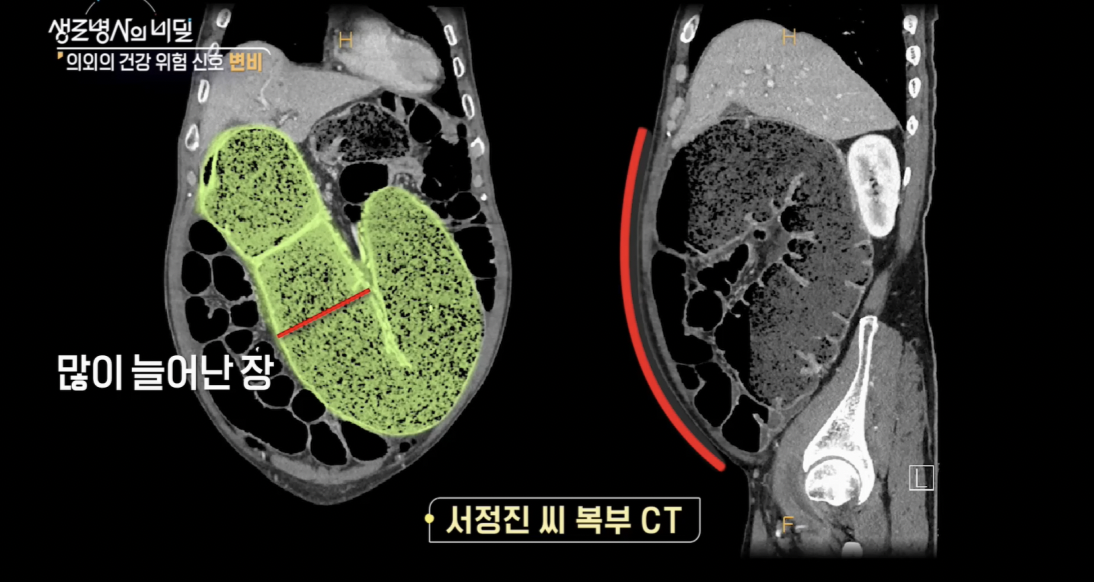

배가 부풀어 오르는 극심한 복통에 뒹굴어야 했던 서정진 씨.

잦은 응급실행 끝에 그에게 내려진 진단은 가성 장폐색이었다.

가성 장폐색은 장이 막히지 않았는데도 장폐색 증상을 보이는 질환으로,

방치하면 장 괴사로 이어져 생명을 위협할 수도 있다.